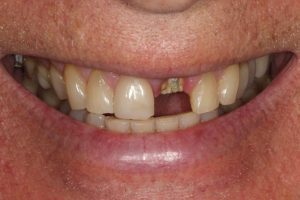

Upper Front Tooth Implant

Both upper front teeth were in a bad way, the upper left one had to be removed as was beyond repair, this was replaced with an implant and a temporary crown on the same day; the upper right front tooth was repaired with a crown. Photos show the result with the definitive crowns after 3 months of treatment.